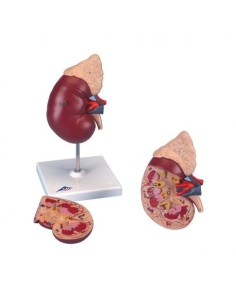

Dal cranio in 22 parti con incastri magnetici ai modelli di colonna vertebrale, da quelli di articolazioni a quelli di cuore, ogni pezzo della nostra collezione è progettato per un’immersione totale nello studio dell’anatomia umana. I nostri modelli, realizzati tramite scansioni di ossa vere, garantiscono un’esperienza tattile autentica e una fedeltà di peso quasi identica agli originali.